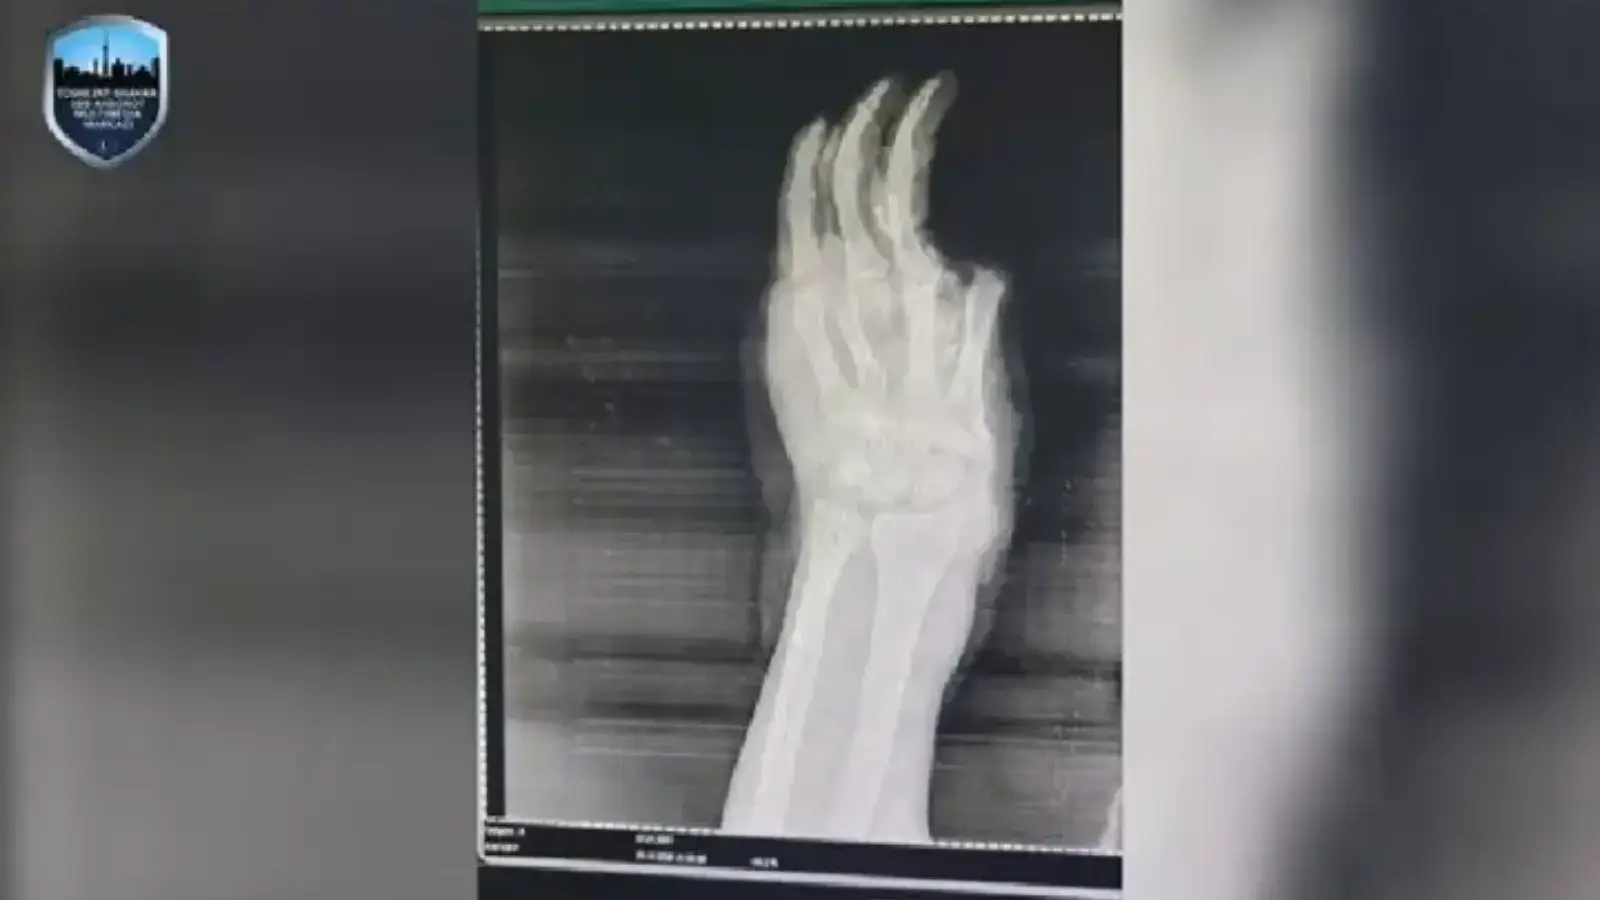

Портлаш оқибатида боланинг танасининг турли жойларида куйишлар кузатилган, шунингдек жароҳатланган қўлдаги бир нечта бармоқ узилиб кетган. Энг оғир томони — қўл панжасидаги барча суяклар майдаланиб, тўқималар жиддий шикастлангани сабаб шифокорлар панжани ампутация қилишга мажбур бўлган.